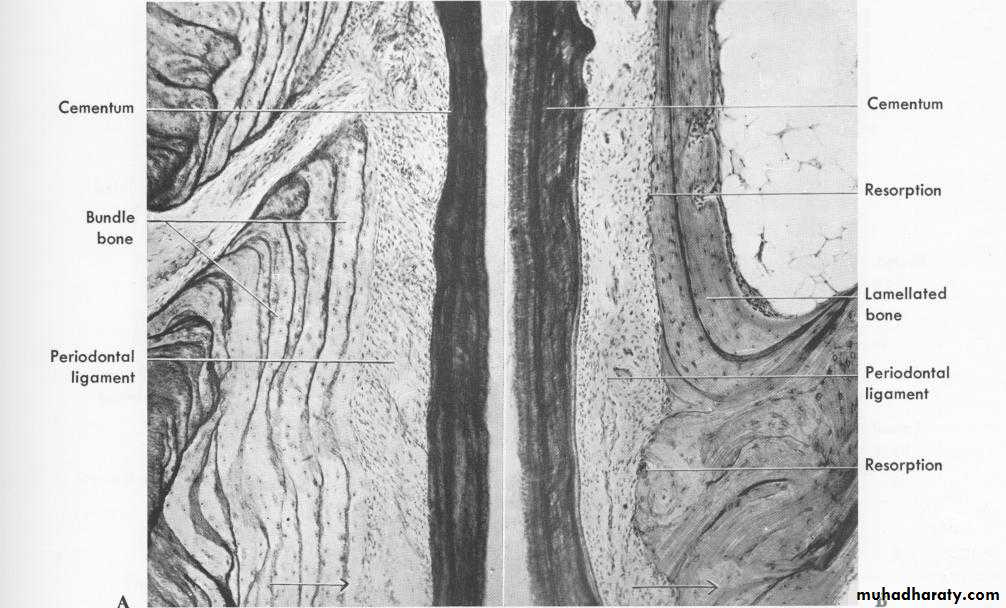

• a-bundle bone• Part of the alveolar bone where periodontal ligament fibres are inserted (attached).

• Sharpey’s fibres – principal fibres of the periodontal ligament that are embedded in the bone and cementum.

• Sharpeys fibres are seen perpendicular to the bundle bone.

• Other fibrils are less and are arranged parallel to the bundle bone surface.

• Histologically, the bundle bone contains fewer fibrils than lamellated bone, therefore it appears dark in hematoxylin and eosin stain. These fibrils are arranged at right angles to sharpey's fibers.

• b-Lamellated bone

• Its a thicker layer consist of bone lamellae which are arranged mostly parallel to the surface of the adjacent marrow spaces. Some of the lamellae form a haversian systems.• 2-The supporting alveolar bone :-